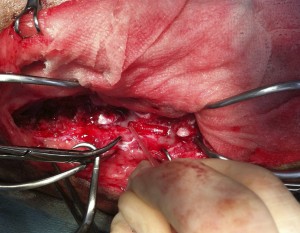

尿道断裂

完全断裂した膀胱と尿道

整復後の膀胱